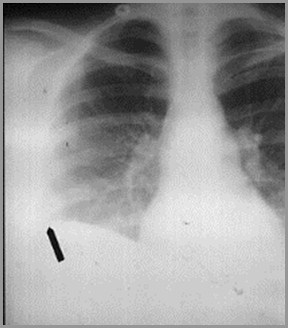

Subpulmonic Pleural EffusionOn the frontal film, the highest point of the apparent right hemidiaphragmis displaced laterally (it is usually in the center). On the lateral film, thereis a flat edge where the effusion meets the major fissure

Subpulmonic Effusion

Usually less than 300-350cc

Accumulates at base of lung betweenvisceral and parietal pleura

Causes apparent lateral displacement ofhighest part of hemidiaphragm

Flat-edge sign on lateral

Increased distance between stomachbubble and base of lung